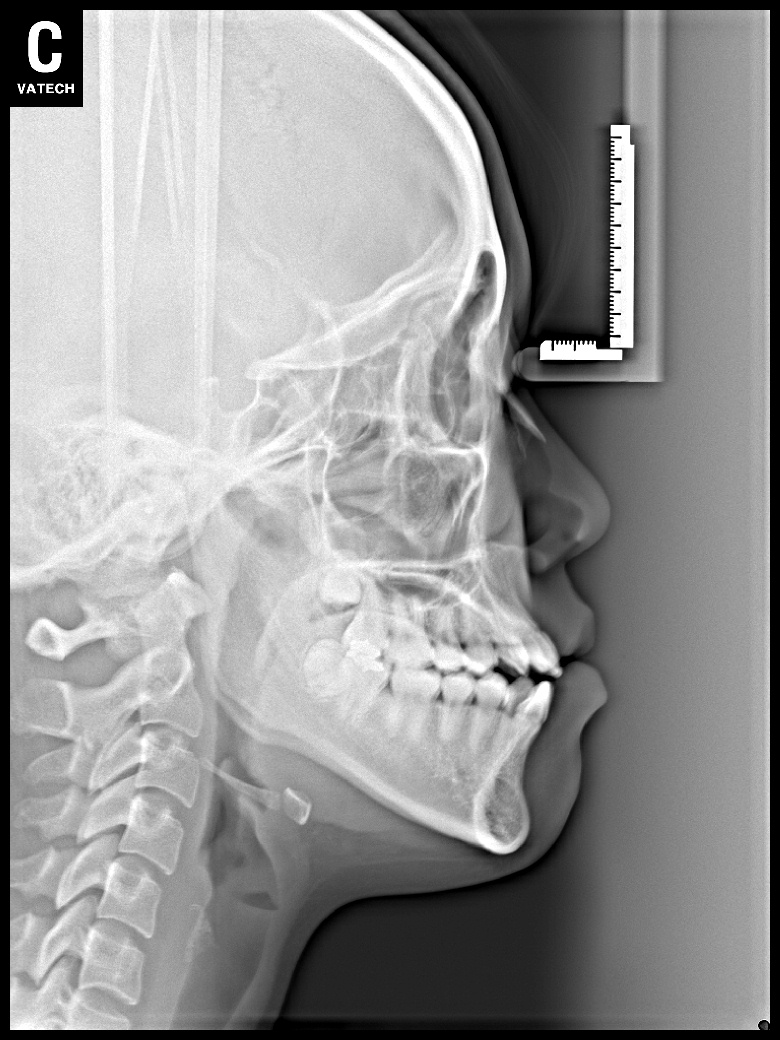

치료 전 사진입니다.